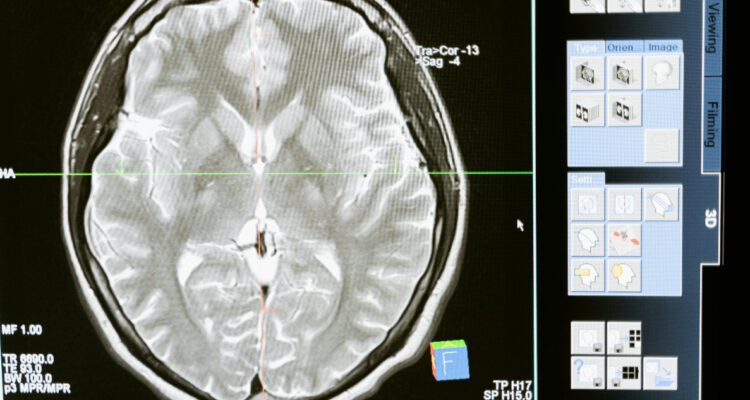

Existen métodos como resonancias magnéticas intraoperatorias o agentes de imágenes fluorescentes para identificar tejido tumoral, pero tienen ciertas limitaciones que no las hacen muy accesibles. De hecho, la maquinaria intraoperatoria no está disponible en todas partes y el método con fluorescencia no funciona en todos los tipos de tumores.

Una imagen de FastGlioma en “modo rápido”, es decir, con resolución más baja, toma solo 10 segundos, y una en resolución completa puede demorar alrededor de 100 segundos, menos de 2 minutos.